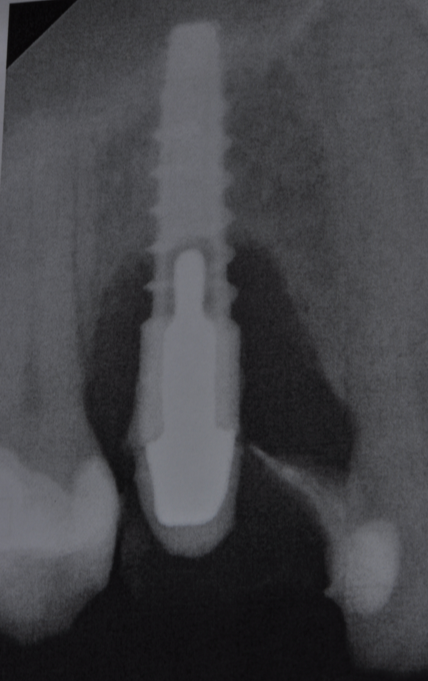

The parameters used to define peri-implant disease usually are: Probing Depth (PD), Crestal Bone Loss (CBL), Bleeding on Probing (BOP) and presence of suppuration and/or fistula.9 Peri-implant mucositis is characterised by soft tissues inflammation witnessed by BOP with or without PD deepening but no effects on the crestal bone while peri-implantitis is characterised by CBL, BOP alone or in conjunction with pus, with or without PD deepening. (Figs. 1, 2 and 3) display the diagnostic steps of a case of peri-implantitis. While mucositis allows a complete healing, peri-implantitis is not reversible.12

Crestal Bone Loss sets another ambiguous point because an adaptive change of the marginal bone level is known to occur afterimplantplacement and restoration.1It’s necessary to agree a baseline for the radiographic evaluation of bone level changes and set an acceptable bone loss rate. Basing on longitudinal clinical studies, it’s rational to chose the time of prosthesis installation as a reference from which the disease can be diagnosed and followed.14 Basing on Albrektson and Zarb review, 1.5mm of bone loss in the first year and less than 0.2mm annually are considered success criteria.1 A CBL exceeding this rate testifies the risk of implant failure. Don't forget that intra-oral x-rays allow to evaluate the interproximal bone level only, missing an appropriate vision of the buccal/lingual sides, where probing becomes essential. Bleeding on Probing is the key parameter for peri-implant disease diagnosis.13 Presence of BOP can be found in 91% of implants with peri-implantitis and its absence is regarded as a reliable predictive parameter of implant health.12

Fig.3: Case 1. X-ray testifying severe peri-implant CBL.

So far, there is no scientific evidence supporting the efficacy of this coadjuvant. The tested protocol consist of a Multiple Anti Infective Non Surgical Therapy (MAINST) that involves the use topical 14% doxycycline to solve the peri-implantitis acute phase and, after 7 days, a session of Full Mouth Air Polishing Therapy (FM-EPAPT) through erythritol powder (Fig.7), a piezo-ceramic device with a PEEK tip (Fig.8), the curettage of internal pocket line (Fig.9) and a second application od Doxy. The patients were further followed with quarterly maintenance sessions carried on with the same FM-EPAPT protocol. Up to 12 months BOP and mean PD decreased significantly and successfully, accompanied by a gain of attachment level up to 12 months. The first case-series about MAINST is waiting to be published and the results are encouraging. Figure 10 and 11 show the healing at 6 and 12 months after MAINST protocol of the peri-implantitis case displayed at the beginning of this article (Fig.1,2,3,4) and figure 12-21 show a complete MAINST case.